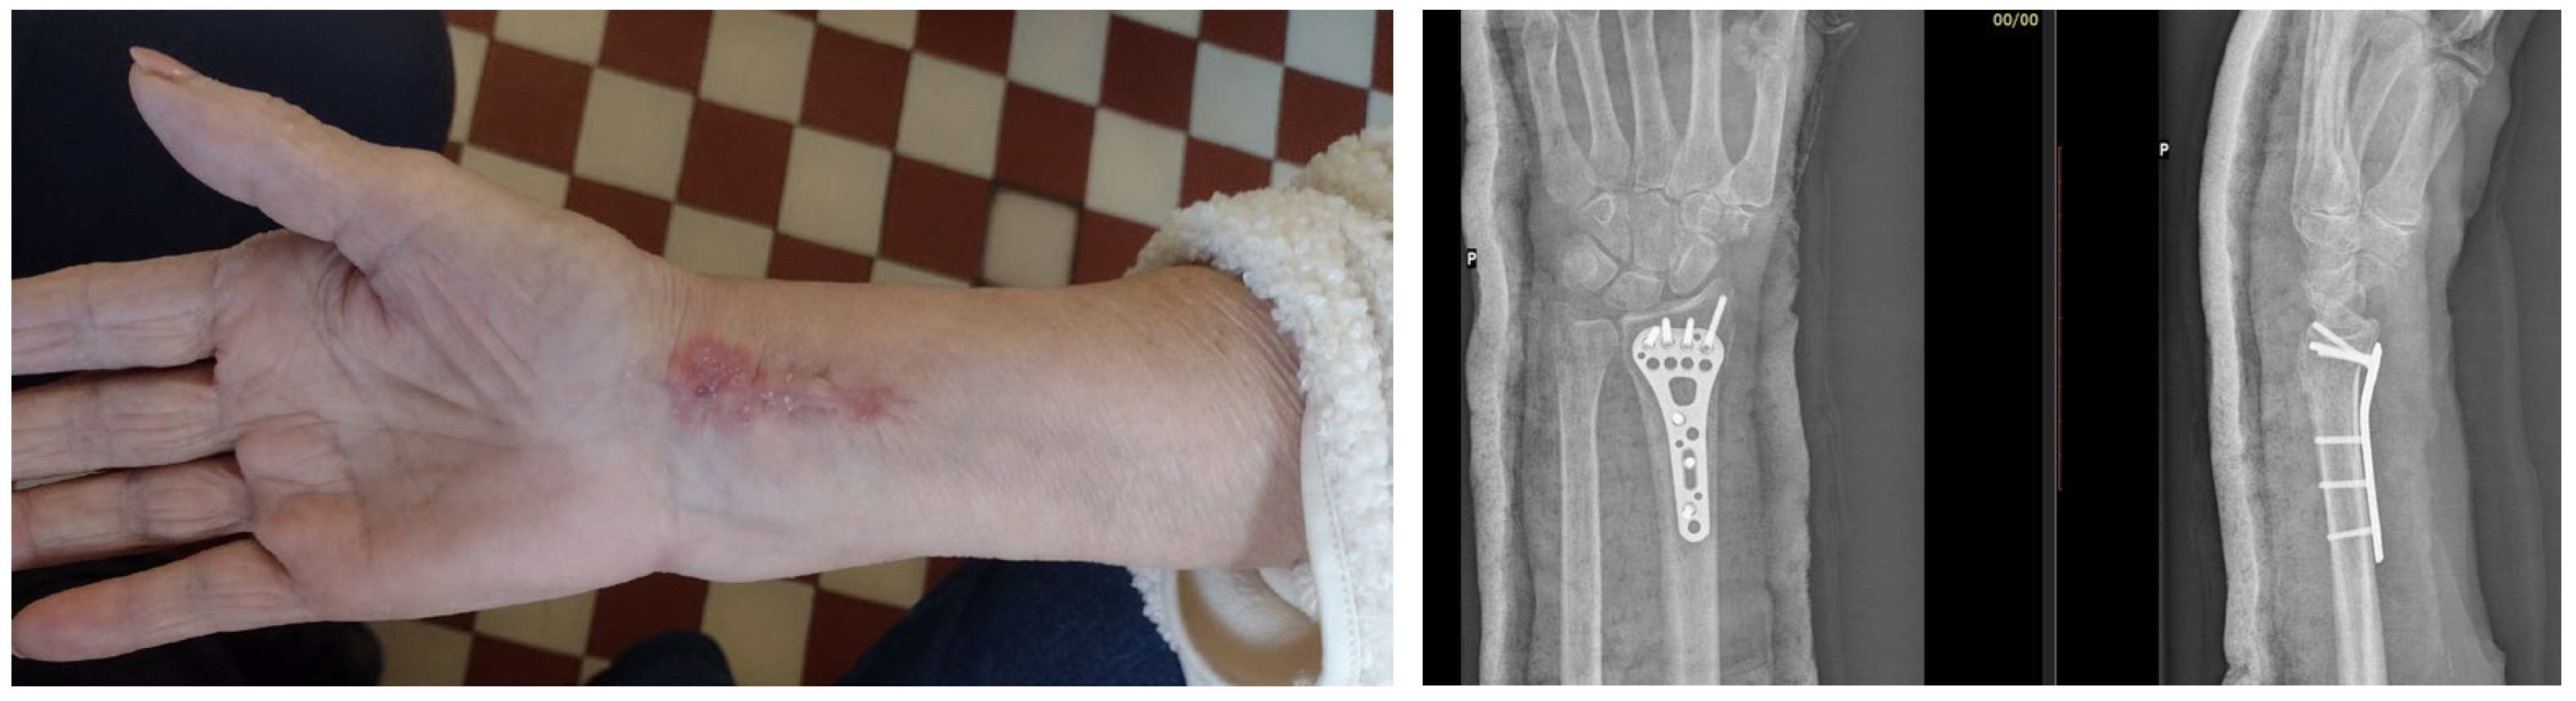

7. Macroscopic Observations of Interacted Surfaces of Removed Implants—Author Observations